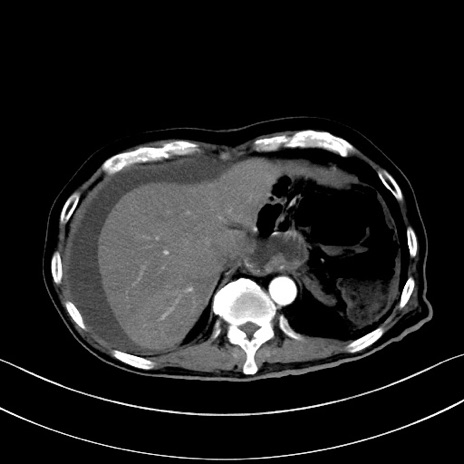

冠状断像

【症例】60歳代男性

【主訴】嘔吐

【現病歴】胃癌にて胃全摘後。食思不振が悪化し、夜中に嘔吐することがある。

【既往歴】胃癌、胃全摘、脾摘、胆摘後

【データ】WBC 5900、CRP 10.56